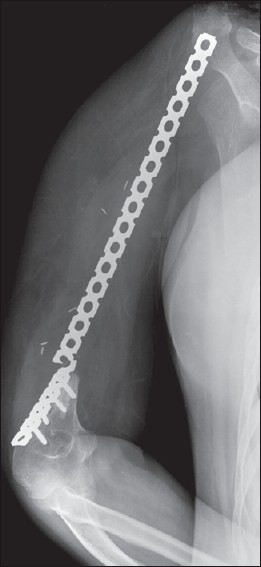

Since January 2006 we have used this technique in eight patients [Table 1]. The follow up for survivors ranges from 10 months to 33 months (mean 20.5 months). Except for the first case, in whom a conventional reconstruction plate was used which broke at 13 months [Figure 3] we have not had any implant complications. | Figure 3: Plate breakage (case: 1) at 13 months when a conventional reconstruction plate was used

Click here to view |